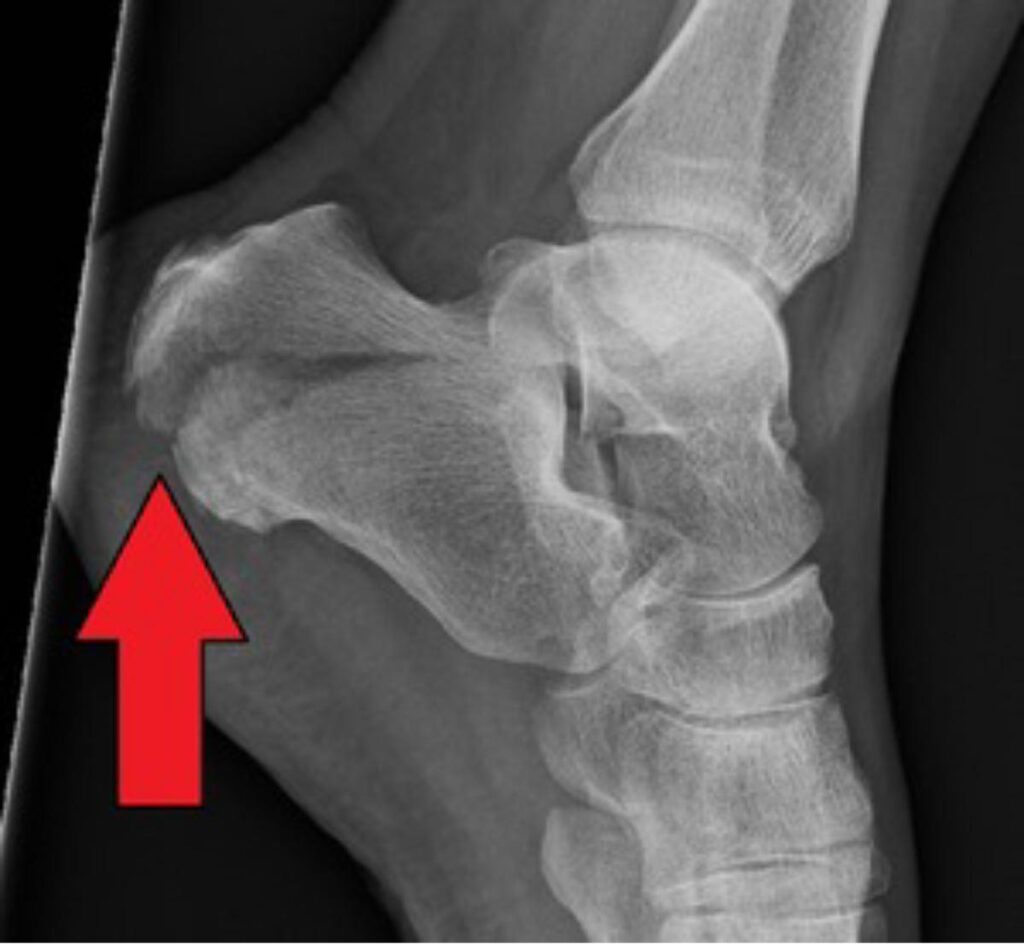

Calcaneal fractures account for 60% of tarsal fractures, and intra-articular fractures account for up to 75% of those. Displaced intra-articular calcaneal fractures are often accompanied by long-term sequelae, permanent disability and other adverse conditions, particularly wound complications such as dehiscence, heel necrosis, hematoma; and infection, and 6.1% of those with infections subsequently developed deep infection and osteomyelitis. Thus, predicting the prognosis of calcaneal fractures can effectively improve post-op recovery and reduce pain in patients.